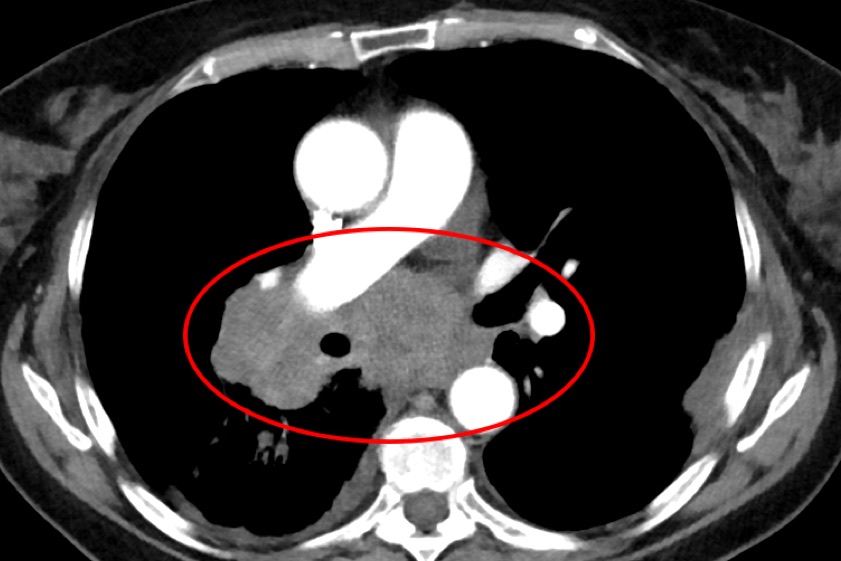

Aufnahme eines kleinzelligen Lungenkarzinoms, das zentral wächst und insbesondere den rechten Hauptbronchus einengt. Fotos: Klinikum Ingolstadt

"Ich sehe, dass in der Corona-Pandemie Vorsorge-Untersuchungen und diagnostische Abklärungen insgesamt seltener wahrgenommen werden", berichtet Lars Henning Schmidt, Direktor der Klinik für Pneumologie, Beatmungs-Medizin und thorakale Onkologie. Seit Beginn der Pandemie sehe er in seiner Klinik mehr Lungenkrebsfälle in weit fortgeschrittenen und metastasierten Stadien als noch vor Corona. "Bösartige Lungentumore zählen ohnehin schon zu den häufigsten und gefährlichsten Krebsarten weltweit", erklärt das Klinikum dazu. "Waren vor Beginn der Pandemie bei rund einem Viertel aller Patienten noch keine Metastasen nachweisbar, so beobachte ich, dass der Anteil dieser Patienten seit zwei Jahren nur noch etwa ein Zehntel beträgt", bedauert der Chefarzt. Ähnliche Beobachtungen zur Schwere der Erkrankungen teilen eine Reihe weiterer Spezialisten am Klinikum Ingolstadt.